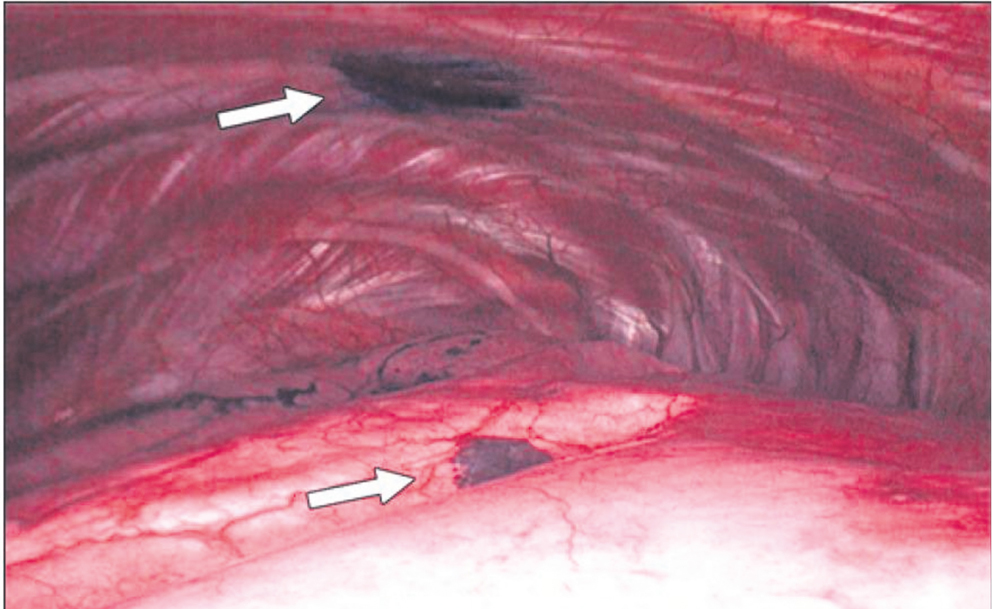

Сразу после введения красителя в зону «периферического инфильтрата» пациент доставлялся в операционную. Далее, под общей комбинированной анестезией с раздельной интубацией бронхов и искусственной однолегочной аппаратной вентиляцией, в условиях тотального коллапса легкого выполнялось оперативное вмешательство — видеоторакоскопическая атипичная резекция легкого в проекции подкрашенного участка (рис. 2).

Рис. 2. Интраоперационное фото, пациент В., 59 лет. Участки маркировки париетальной и висцеральной плевры 1 % водным раствором метиленового синего (белые стрелки)

Fig. 2. Intraoperative photograph, Patient V, 59 years old. Areas of parietal and visceral pleura marking with 1% aqueous methylene blue (white arrows)